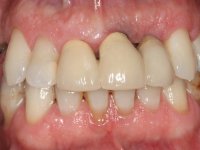

Patient male, 60 years old, non-smoker. After imaging and clinical examination, it was found that the patient had teeth 2.1 and 2.2 with extensive acrylic restorations, with screwed intra radicular posts and very poor endodontic treatments. Tooth 2.2 had an extensive apical lesion, the post had been placed on a false route and had mobility. Tooth 1.1 had an extensive resine restoration and tooth 1.2 presented a mesial restoration, also in composite resin, Class III type. The antero-superior sector was vestibularized, as consequence of a loss of vertical occlusion dimension associated with posterior edentulism. The patient showed reasonable periodontal health and satisfactory oral hygiene.

In view of the clinical situation presented, an oral rehabilitation was proposed that contemplated the antero-superior situation but also the lack of posterior teeth, seeking a more comprehensive functional and aesthetic rehabilitation. However, this proposal was not accepted, and therefore the intervention had to be restricted to the upper-antero sector. Obviously, the limitations of this intervention were explained to the patient. Thus, it was proposed to perform the endodontic treatment of tooth1.1 and to redo tooth 1.2, including: placing an intra-radicular post on 1.1 and a cast post and core in 2.1; place a provisional bridge with 3 elements with teeth 1.1 and 2.1 as abutment teeth and 2.2 as a pontic. This provisional would allow to rehabilitate the situation between the extraction of tooth 2.2 and the placement of an implant in its place. Work would be finished with 3 metal-ceramic crowns, two on teeth 1.1 and 2.1 and another on the implant placed in the site of the tooth 2.2.

Endodontic treatments were performed and a metalic non screwed intra radicular post was placed on tooth 1.1. An alginate impression was made for laboratory confection of a reinforced acrylic provisional bridge, with teeth 1.1 and 2.2 as abutments and 2.2 as a pontic. After preparation of tooth 1.1 and root preparation of 2.1, the bridge was relined in mouth with self-polymerizable acrylic using a metal post for further retaining the prepared root canal on 2.1. Tooth 2.2 was cut at the gingival level to function as support. In the same session, the impression of the root canal of the 2.1 was made for the laboratory confection of a cast post and core. A double mixture technique with plastic tutor was used after previous canal vaseline with endodontic file and cotton. The provisional bridge was provisionally cemented and the cast post and core was made in the laboratory. Cast post and core cementation was made with resin-reinforced glass ionomer cement and the provisional bridge had to be readjusted to the new situation by removing the post at the site of 2.1. After careful surgical planning, a dental implant was placed, simultaneously with extraction of the root of tooth 2.2. The provisional bridge was placed by resting on the healing screw placed in the implant. The respected osteointegration period was 12 weeks, during which the provisional bridge was relined twice. After complete maturation of hard and soft tissues, definitive impressions were made. The gingival retraction technique was applied with an impregnated retraction cord and impression was performed using double mixture, open tray impression technique. A custom precious metal abutment implant was prepared in the lab, along with 3 metal caps to be used as infrastructures for the metal ceramic crowns. Particular care was taken in the confection of the cervical finishing line of the implant abutment, in order to follow the soft tissues emergence profile. Proof of infrastructures was done in the mouth being evaluated clinically and imagiologically. Collection of color information was done by the ceramist at the office. Ceramic was applied in the laboratory and the finished work was placed in the mouth after approval by the patient. Definitive cementation was made with resin-reinforced glass ionomer cement, and the first crown to be cemented was that of the implant, to facilitate removal of the excess.